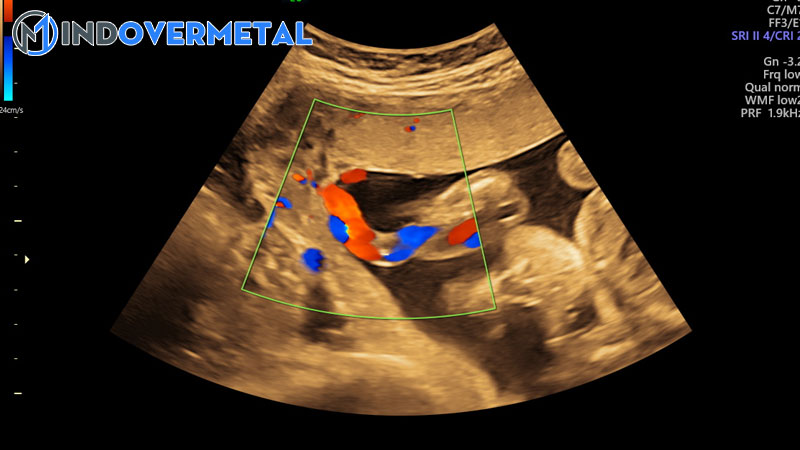

Dây rốn bám màng

Dây rốn bám màng khá hiếm gặp, chỉ xảy ra ở khoảng chừng 1 % những trường hợp mang thai đơn và 9-15 % thai kỳ song thai. Do bám trực tiếp vào màng ối nên mạch máu thai nhi từ dây rốn phải đi qua màng ối, màng đệm trước khi đến được bánh nhau. Điều này sẽ làm giảm lượng dinh dưỡng cung ứng cho thai nhi từ bánh nhau, có trường hợp thai nhi chỉ nhận được tối đa 30 % dinh dưỡng. Điều này sẽ dẫn đến rủi ro tiềm ẩn suy dinh dưỡng bào thai, sinh non, thai lưu .

Nguy hiểm hơn, trong trường hợp dây rốn bám màng, những mạch máu của dây rốn thai nhi phải hoạt động giải trí mà không có sự bảo vệ của lớp thạch Wharton, nên dễ bị chèn ép và đứt ra khi có ảnh hưởng tác động. Ngoài ra, rủi ro tiềm ẩn tử trận của thai nhi là rất cao trong lúc chuyển dạ vì những mạch máu này dính rất chặt vào lớp màng đệm nên dễ vỡ ra khi có cơn co tử cung, vỡ tự nhiên hoặc khi bấm ối.

Như vậy hoàn toàn có thể thấy dây rốn bám màng là một thực trạng hiếm gặp trong sản khoa nhưng lại vô cùng nguy hại với thai nhi .Tình trạng dây rốn bám màng thường chỉ phát hiện qua siêu âm hoặc sau khi mổ lấy thai vì suy tim thai trong quy trình chuyển dạ ( do mạch máu thai nhi bị vỡ hoặc chèn ép dẫn đến thiếu máu nuôi dưỡng bào thai ) .